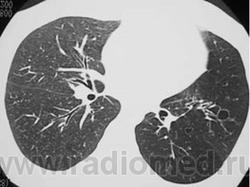

Swyer-James syndrome - эмфизема легких, при которой обычно поражается только одно легкое; болезнь чаще всего начинается в детстве или в юности. Развивается после перенесенного некротического бронхита и, по мнению специалистов, вероятнее всего, ее причиной является присутствующий в организме вирус.